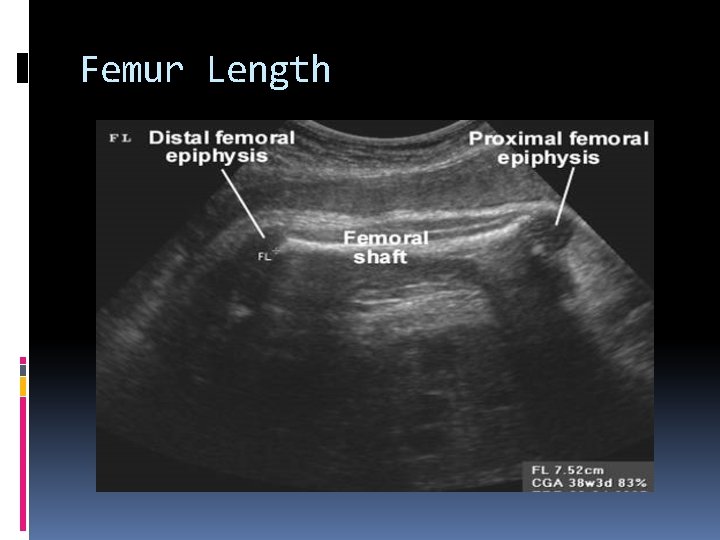

FL Femur length Best obtained with a linear array transducer (eliminates artifactural bowing due to sector beam geometry. Includes only ossified diaphysis, excludes Epiphyseal cartilage. If femur length falls below 2 SD of the mean, short limb dysplasia may be present, and other long bones should be measured.

Femur Length

Epiphyseal Appearance Gestational age can be estimated by identifying the presence of ossification centers within various epiphyses. The identification of ossified epiphyses can be helpful in cases where the other parameters are not concordant or when dates are uncertain. Distal femoral Epiphyseal appearance (DFE) can be seen at 33 weeks Proximal tibial Epiphyseal appearance (PTE) can be seen at 35 weeks Proximal humeral Epiphyseal appearance (PHE) can be seen at 38 weeks